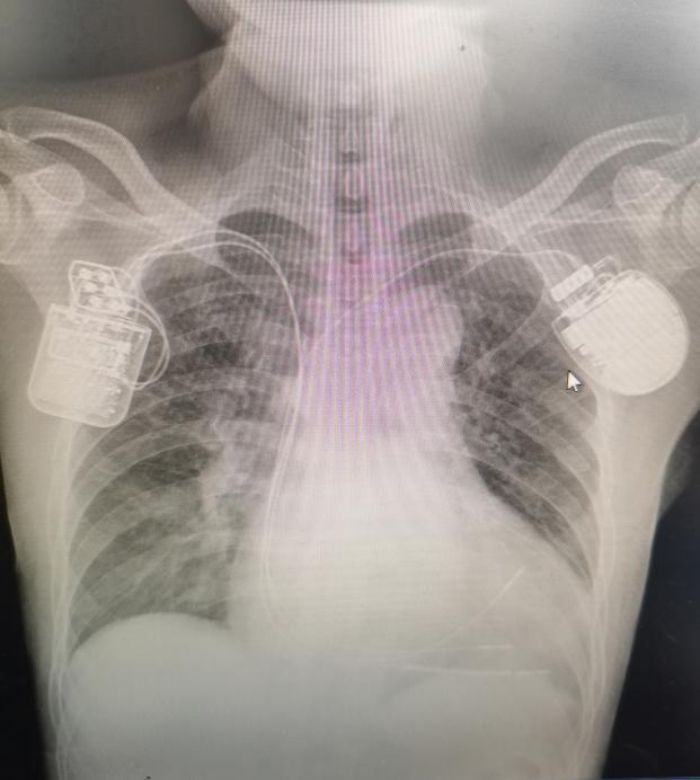

近日,江西省人民医院(南昌医学院第一附属医院)-省心血管病医院四病区负责人李林锋团队成功为一例扩张型心肌病合并阵发性室速的患者实施一站式CCM(心脏收缩力调节器)联合ICD置入术,取得良好的疗效。该一站式手术的成功开展,充分体现了我院心血管内科先进的治疗理念及高超的技术水平,也为药物治疗效果欠佳的心衰患者带来了“心”希望。

在省心血管病医院常务副院长赖珩莉的指导下,李林锋、刘元庆与团队人员密切配合,于4月10日顺利开展该例一站式手术。首先从左侧完成心尖部除颤电极的植入;然后从右侧先后将两根5076-58cm螺旋电极植入右室高位间隔及中位间隔部;最后,测试低位间隔电极的起搏阈值0.7V、感知灵敏度14mV、阻抗580Ω,高位间隔电极的起搏阈值0.6V、感知灵敏度10mV、阻抗600Ω,联合测试三根电极均可正常工作且彼此无干扰。整个手术过程进展顺利,共耗时100分钟。